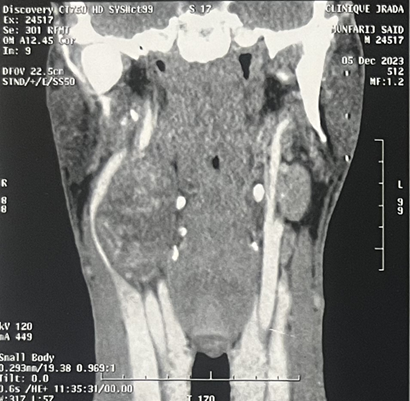

Magnetic resonance imaging (MRI)

of the neck confirmed a 39x38x60 mm properly limited mass with high signal

intensity on T1-weighted MRI and a heterogeneous, low signal intensity on T2

weighted MRI (Figure 1). After

intravenous administration of gadolinium-based contrast material, the lesion

showed irregular peripheral enhancement. Carotid artery angiography was

performed because of the close relationship between the mass and the carotid

artery. The angiography showed a normal filling in the right common, internal,

and external carotid arteries and their branches. (Figure 2).

Figure 2: Coronal (A) sagittal (B) and axial(C) view. Gray

arrow: well-circumscribed, h mass with dimensions of 39x38x60 mm in the right

lateral cervical region directly under the right sternocleidomastoid muscle,

separating the internal jugular vein and the carotid artery. Yellow arrow:

compressed internal jugular vein. Black arrow: carotid artery.